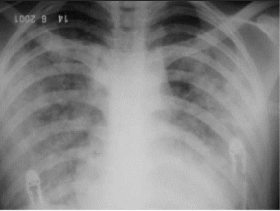

Paciente de 65 anos, sexo feminino, 50 kg, com história de diabetes, HAS e neoplasia de mama foi admitida com insuficiência respiratória aguda e diagnóstico de broncopneumonia, iniciado antimicrobianos, coletado culturas e subsequentemente intubada, após tentativa de ventilação não invasiva sem sucesso. Está ventilando com VC: 300ml, peep: 8, FR: 22. A gasometria arterial com FIO2: 70% é a seguinte: pH: 7,28, pCO2: 62, pO2: 84 e o RX tórax encontra-se em anexo abaixo. Submetida à punção de acesso venoso central com PVC: 16. Iniciado baixa dose de vasopressores (noradrenalina) por hipotensão e no momento PAM: 65mmHg. A diurese diminuiu para 0,3ml/Kg nas últimas 6 horas. Qual será o próximo passo no manuseio da paciente?

RX tórax 24 hrs após a admissão da paciente

Figura 2 - Radiografia de tórax 24 horas após internação mostrando maior confluência das consolidações